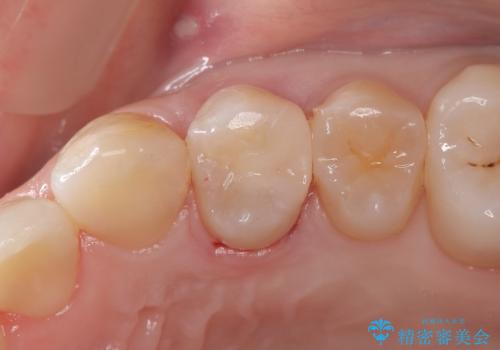

見落としやすい虫歯(コンタクトカリエス)を発見|精密診断で早期治療

左上7のメタルインレーを除去|セラミッククラウンで自然な美しさと機能回復